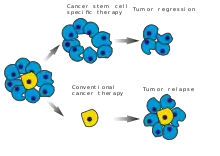

Cancer stem cells and drug resistance

Scientists have discovered a molecule on the surface of tumors that appears to promote drug resistance—by converting the tumor cells back into a stem cell-like state.

When the tumor cells began to exhibit drug resistance, the cells were simultaneously transforming into a stem cell-like state, which made them impervious to the drugs. It appeared that the treatment itself was driving this transformation by activating a specific molecular pathway. Luckily, several existing drugs, such as Bortezomib for example, can attack this pathway and reverse the cellular transformation, thus 're-sensitizing' the tumor to treatment.[19][20][21]